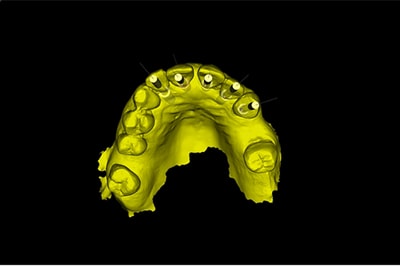

Chirurgie Guidée

L’implantologie moderne évolue vers un positionnement des implants dicté par la prothèse. Il permet et garantit un meilleur résultat esthétique, une meilleure distribution des forces et une hygiène facilitée. La combinaison de l’imagerie 3D et de logiciels de planification autorise des études préliminaires d’une grande finesse. On pourra ainsi visualiser la faisabilité prothétique d’un plan de traitement implantaire.

Au cabinet, pour les cas complexes, après réalisation d’une imagerie 3D (scanner ou cone beam), le cas sera étudié (avec un logiciel de planification), et une solution sera proposée. Dès validation, un guide chirurgical sera confectionné, dans l’absolu respect de la planification. Il permettra de positionner et placer chaque implant dans la position et l’axe pré-défini.

Plusieurs types de guides sont possibles. S’il reste des dents sur l’arcade, nous réaliserons un guide dento-porté (stable et précis). S’il ne reste aucune dent, nous devrons réaliser un guide ostéo-porté.